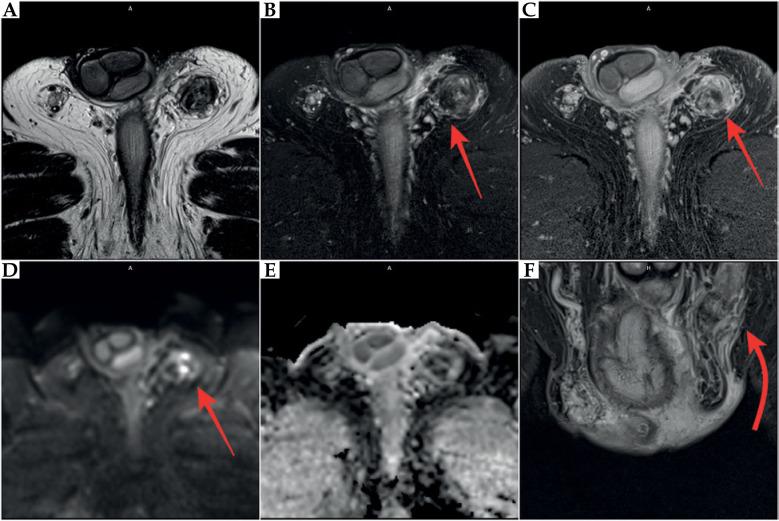

The aim of this paper was to present a rare complication of orchiepididymitis in a patient treated with brachytherapy (BT) for prostate cancer, who underwent trans-ureteral resection of the prostate (TURP) four weeks after BT. A 73-year-old patient with prostate cancer (intermediate-risk group) was eligible for high-dose-rate (HDR) BT combined with androgen deprivation therapy (ADT) for 6 months (leuprorelin). Due to increased symptoms, such as urinary retention after BT, the patient required catheterization. Additionally, bacterial inflammation in the lower urinary tract and prostate was present. Due to prolonged micturition disorders, TURP was performed, leading to chronic orchiepididymitis four months after completion of BT and three months after catheter removal following TURP. Due to long-term inflammation, which was resistant to treatment, the left testicle with left epididymis was removed. Unfortunately, inflammatory symptoms occurred post-operatively in the bed and the left groin. Since these symptoms of varying severity continued, anti-inflammatory drugs and analgesics were introduced. TURP performed too quickly after HDR-BT might cause severe complications. Extreme caution regarding TURP should be exercised in patients undergoing BT. Conservative and pharmacological treatment must be introduced in the occurrence of urinary disorders after BT, and any intervention (TURP) should be performed at least 3-6 months after BT. This is especially crucial because of the development of radiation effect over time.

本文的目的是介绍一名接受前列腺癌近距离放射治疗(BT)的患者发生的罕见附睾炎并发症,该患者在BT治疗四周后接受了经尿道前列腺切除术(TURP)。一名73岁的前列腺癌患者(中危组)符合接受高剂量率(HDR)BT联合雄激素剥夺治疗(ADT)6个月(亮丙瑞林)的条件。由于BT后出现诸如尿潴留等症状加重,患者需要导尿。此外,下尿路和前列腺存在细菌感染。由于排尿障碍持续存在,患者接受了TURP,导致在BT完成四个月后以及TURP后拔除导尿管三个月后发生慢性附睾炎。由于长期炎症对治疗有抵抗性,切除了左侧睾丸及附睾。不幸的是,术后在床上和左侧腹股沟出现了炎症症状。由于这些不同程度的症状持续存在,开始使用抗炎药和镇痛药。HDR-BT后过快进行TURP可能会导致严重并发症。接受BT的患者在进行TURP时应极其谨慎。BT后出现排尿障碍时必须采取保守和药物治疗,任何干预措施(TURP)应在BT后至少3至6个月进行。由于放射效应会随时间发展,这一点尤为关键。